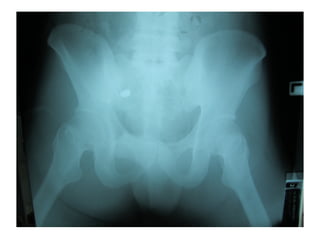

Male 25 yr ถูกยิงที่ท้อง 15 min PTA

ABCD ผ่าน

BP 130/80 mmHg PR 110/min RR 20/min

กระสุนไม่ทะลุอวัยวะภายใน

Secondary survey

GA : A man with good consciousness

HEENT : no pale conjunctiva, no icteric sclera

Heart : regular rhythm, no murmur

Lung : clear

Abdomen : soft, mild tender, no guarding, no

rebound tenderness, active bowel sound

Extremities : no deformities, normal movement

of both hips, no pain on motion

Rt. femoral, popliteal, dorsalis pedis & post

tibial 2+

FAST –ve

Foley’s cath : no blood

NG tube : no blood